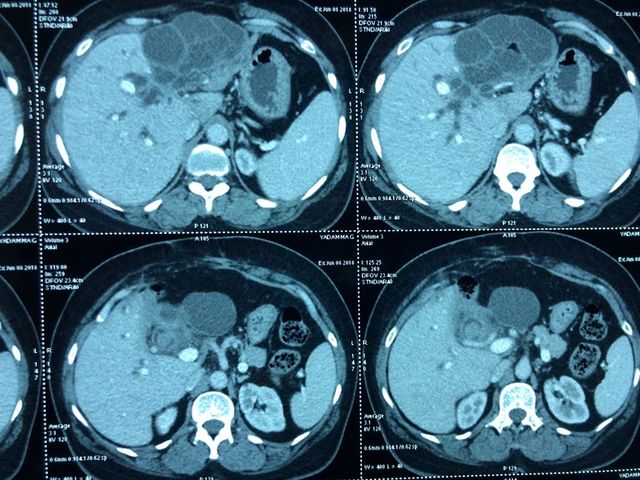

Total pancreaticoduodenectomy with splenectomy done for a 45 yr female with main duct

Total pancreaticoduodenectomy with splenectomy done for a 45 yr female with main duct IPMN with invasive mid-body cancer with bilateral polycystic kidneys. Her EUS, ERCP and fluid cytology , fluid CEA, serum CA19 -9 were all suggestive and a PET showed high uptake in her solid .She is doing well post op but planned for adjuvant CT Rt as had breached capsule and encased splenic vein. Total pancreaticoduodenectomy was frowned upon as a high morbidity surgery due to severe exocrine and endocrine insufficiency with brittle diabetes and ulcerogenicity due to complete loss of pancreatic bicarbonate secretion. But in recent years with easy availability of enzyme supplements, CGM (continuos glucose monitoring devices), insulin pens and long acting PPI the long term QoL of these patients is comparable with partial pancreatectomy patients